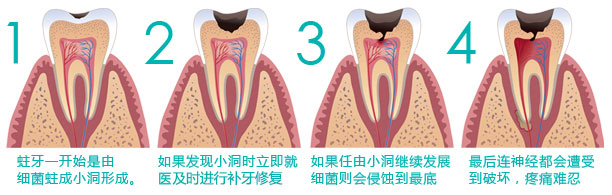

龋齿又叫虫牙,学名蛀牙。其主要形成原因是牙菌斑,牙菌斑是牙齿表面的一层几乎无色的薄膜,含有造成龋齿的细菌。每次进食后,牙菌斑中的这些细菌会和食物中的糖分或淀粉发生化学作用,产生腐蚀牙齿的酸性物质。久而久之,牙齿的珐琅质便会破坏,形成比较脆弱的小蛀斑,若继续恶化则会形成牙洞,即龋齿。

3、蛀牙程度 临床上可见龋齿有色、形、质的变化,而以质变为主,色、形变化是质变的结果。临床上常根据龋坏程度分为浅、中、深龋三个阶段